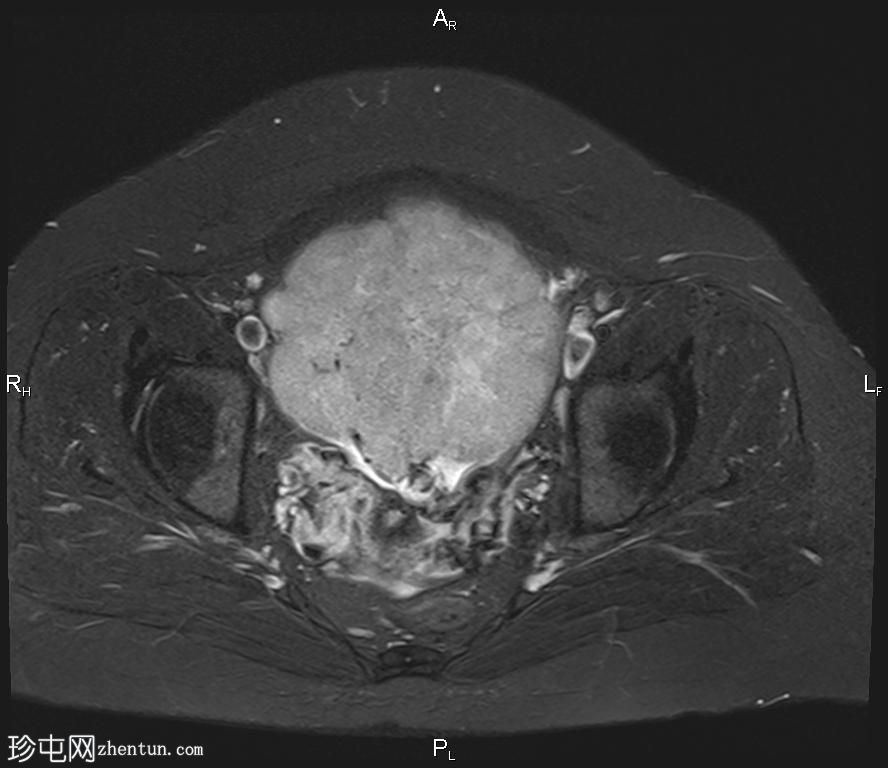

轴向位

T2

盆腔内可见一巨大多分叶实性肿块,内部有隔膜,T2WI信号不均匀,T1WI信号不均匀,呈低信号。肿块内散在分布囊性/坏死性病变。

肿块外可见子宫和右侧卵巢,肿块似源自左侧卵巢。该肿块压迫膀胱和两侧远端输尿管,并导致肠管和血管结构移位,但无侵袭或包裹征象。

造影后,肿块呈不均匀强化,隔膜强化。

远端髂腹旁和两侧髂骨旁区域可见少量肿大淋巴结。